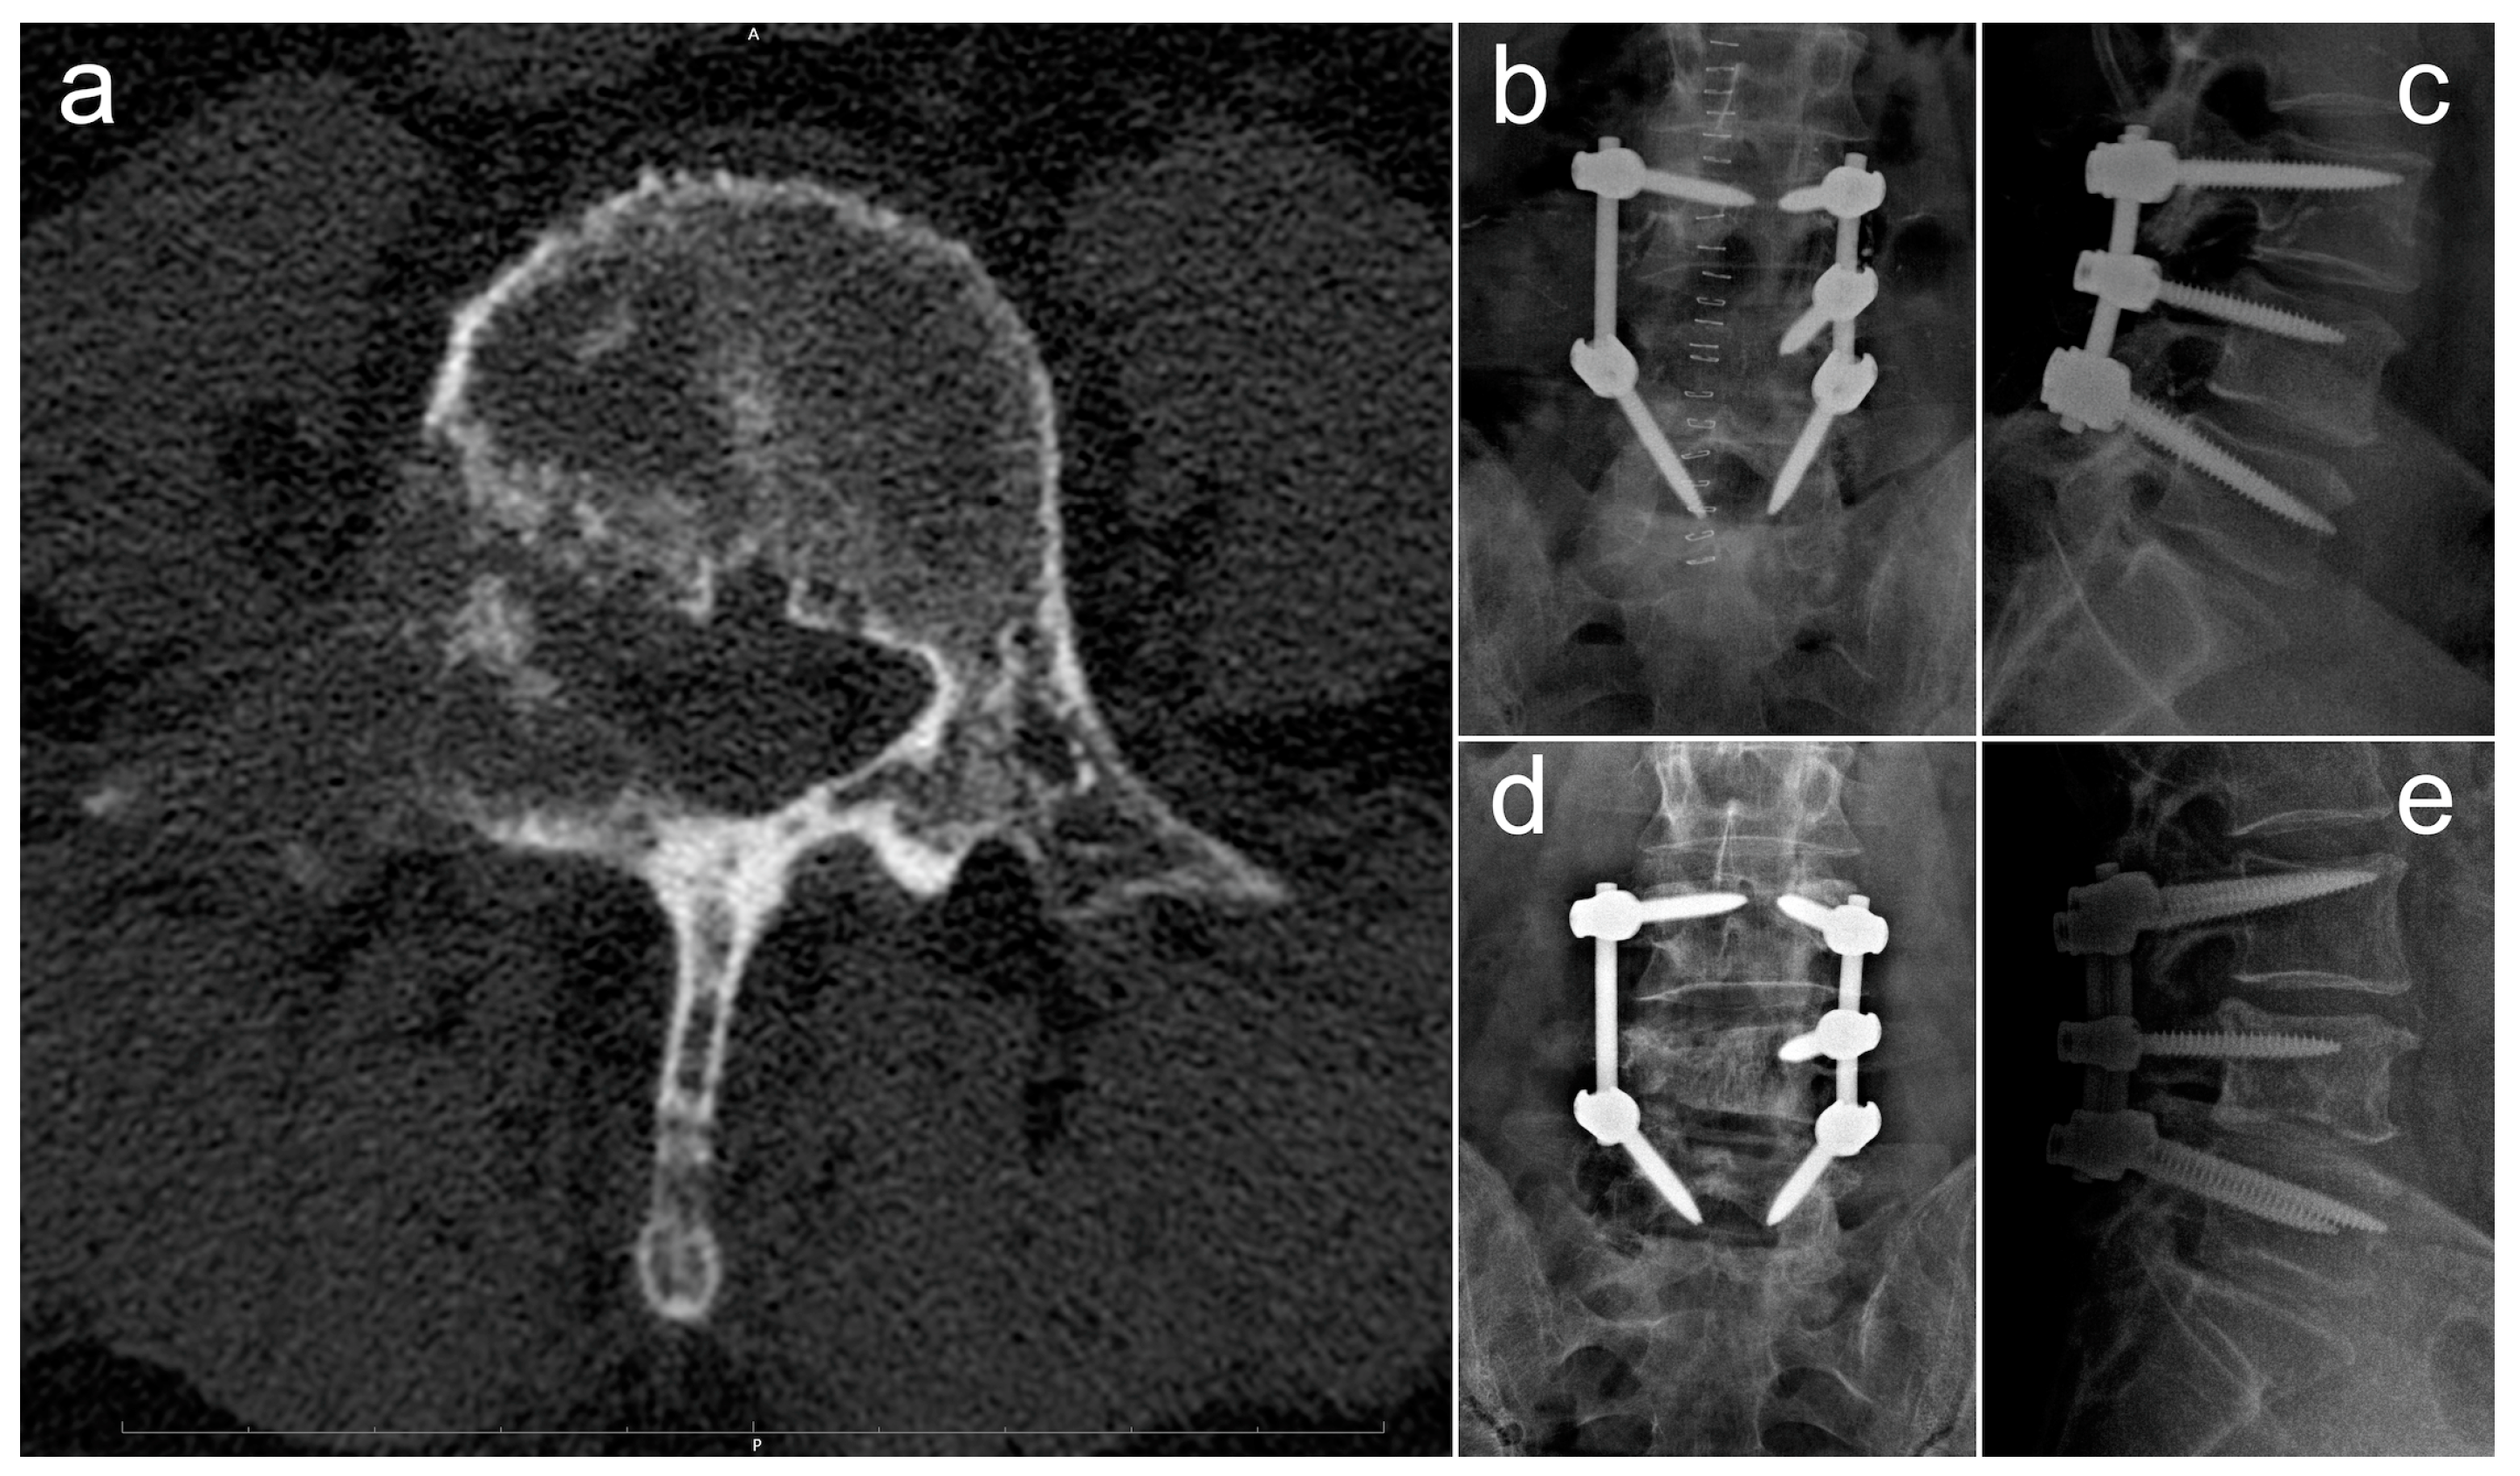

In Figure 4, we report and illustrate a case of metastasis from adenocarcinoma at the L4 level, treated using debulking and stabilization 30 months after the diagnosis of the primary tumor. After surgery, the patient received targeted chemotherapy with osimertinib and radiation therapy and lived for 30 months with a good quality of life (ambulatory status: autonomous, Frankel score E, Karnofsky score 80 at last follow-up).

Figure 4.

Radiographic images concerning a case of an L4 metastatic lesion from adenocarcinoma, treated via debulking and stabilization. (a) Preoperative axial CT scan showing the osteolytic lesion in L4; (b,c) postoperative anteroposterior (b) and laterolateral (c) Rx projections showing L3–L5 stabilization; (d,e) anteroposterior (d) and laterolateral (e) Rx projections at 18-month follow-up.